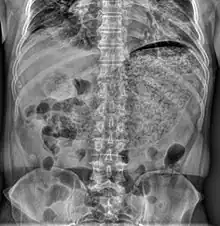

Simple abdominal X-ray reveals a large amount of material in the stomach, suggesting severe gastric hypomotility | |